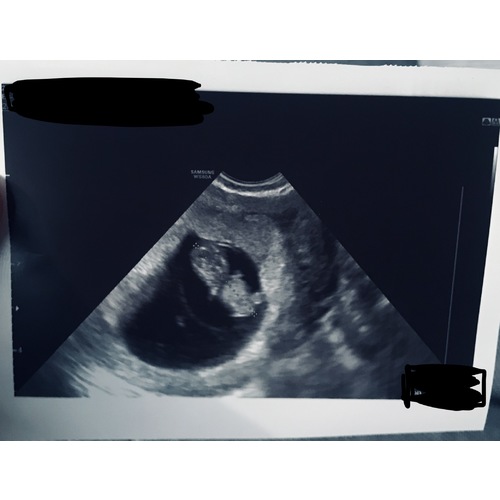

8 weken❤️